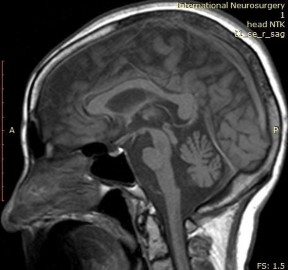

MRI chụp lại lần thứ 2 lúc nhập viện ghi nhận teo cầu não và tiểu não, với dấu hiệu “bánh ngọt chữ thập”.

MRI não ghi nhận teo cầu não và tiểu não với dấu “bánh ngọt chữ thập”